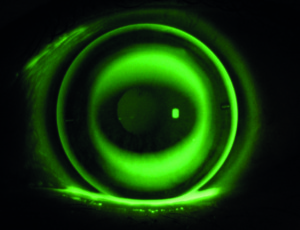

Das hängt vom Zustand des Auges, insbesondere der Hornhaut und des Tränenfilms ab. Bei unseren Messungen, die im Vorfeld der Anpassung stattfinden, beurteilen wir im Detail das Auge. Wir unterstützen in unserem Kundenkreis mehrere Personen mit der Lieferung von Kontaktlinsen, die ein Hornhauttransplantat erhalten haben oder eine LASIK-OP haben durchführen lassen. Hier sind die regelmäßigen Nachkontrollen bei uns und auch beim Augenarzt besonders wichtig.